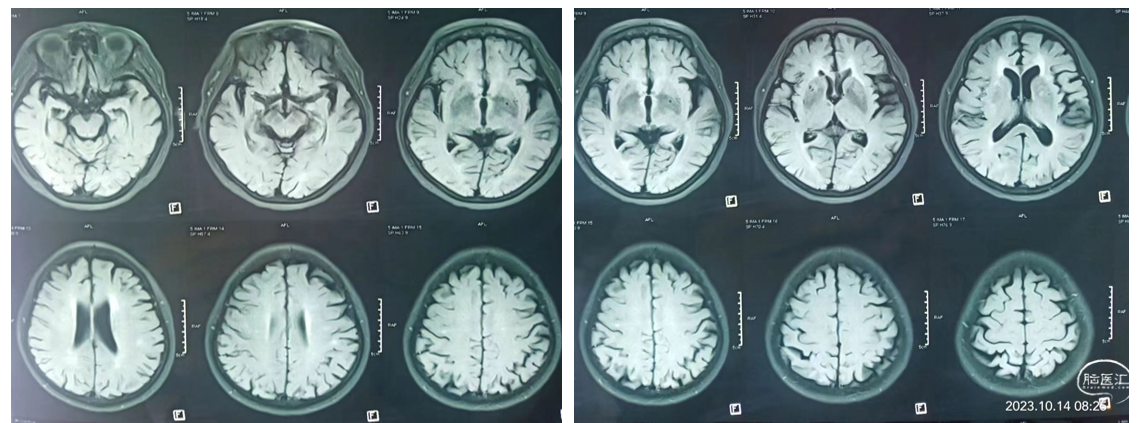

现病史:患者于2小时前突发言语含糊,吐字不清,头晕、头昏,左侧上下肢无力。患者之女自驾车送来我院就诊。既往史:有高血压病史5年余,2年前患右侧基底节区脑梗死经治疗好转,无明显后遗症。专科查体: 意识清,言语含糊,左侧上下肢肌力3级。左侧巴宾斯基(++),NiHSS评分7分。辅助检查:核磁DWI显示:右侧基底节区多发点状梗塞灶,考虑低灌注。MRA显示:右侧大脑中动脉M1段以远端未显影,考虑ICAS病变。

患者老年女性,既往有高血压、脑梗死闭塞,本次急性发病,核磁共振检查:DWI显示多发点状梗死灶,考虑为低灌注。

距离发病2小时,NiHSS评分7分,符合大血管病变,在溶栓和血管内治疗6小时时间窗内,结合病史和检查,考虑ICAS病变。静脉溶栓不能达到血管再通。

患者术后情况:

术后患者意识清,生命体征正常,血压125/80mmHg,言语流畅,肢体肌力5级,病情明显递转,可自行端碗吃饭和肢体活动。

CT检查: